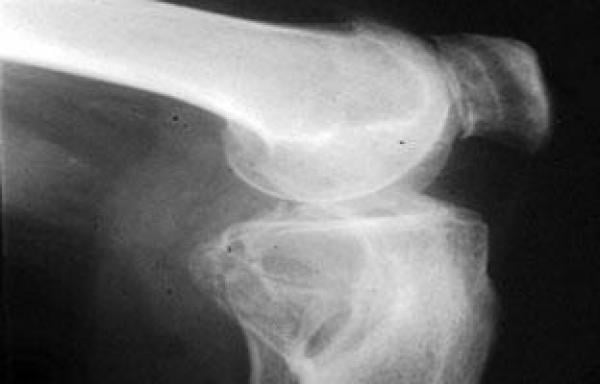

يجيب عن هذا التساؤل الدكتور عبد الحى مشهور أستاذ أمراض العظام قائلا: الارتشاح الدموى للركبة من الإصابات الشديدة التى تحدث تمزقا بالأغشية الداخلية أو الأربطة، وقد تسبب كسرا يصل لسطح مفصل الركبة وينتج عنه نزيف دموى داخل تجويف المفصل، ويظهر التورم خلال ساعة من الإصابة مع ارتفاع درجة الحرارة بواقع درجة أو درجتين.

ولعلاج الحالة يشير مشهور إلى أهمية عرض المصاب على الطبيب للتأكد من عدم إصابة أربطة الركبة ولاستبعاد احتمال وجود كسور تصل للمفصل، وذلك من خلال الأشعة العادية أو يفضل أشعة الرنين المغناطيسى لأنها أكثر دقة.

كما ينصح مشهور بعمل تفريغ للتجمع الدموى بتجويف الركبة، حيث أن عدم إزالته يؤدى إلى حدوث آثارا ضارة بالغشاء السينوفى ثم يتم عمل جبس فوق الركبة لمدة أربعة أسابيع.